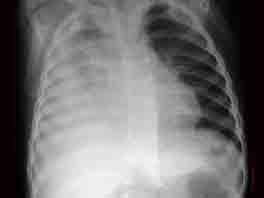

问题 1岁半男孩,出生时已种卡介苗,热一周不退,今体温40度,咳喘突然加剧,唇绀,嗜睡WBC29×10/L,N72%,L28%,摄胸片结果见图,最可能的诊断是 ( )

选项 A、结核性胸膜炎 B、急性支气管肺炎并心衰 C、急性毛细支气管炎 D、病毒性肺炎 E、金黄色葡球菌肺炎并脓胸

答案 E